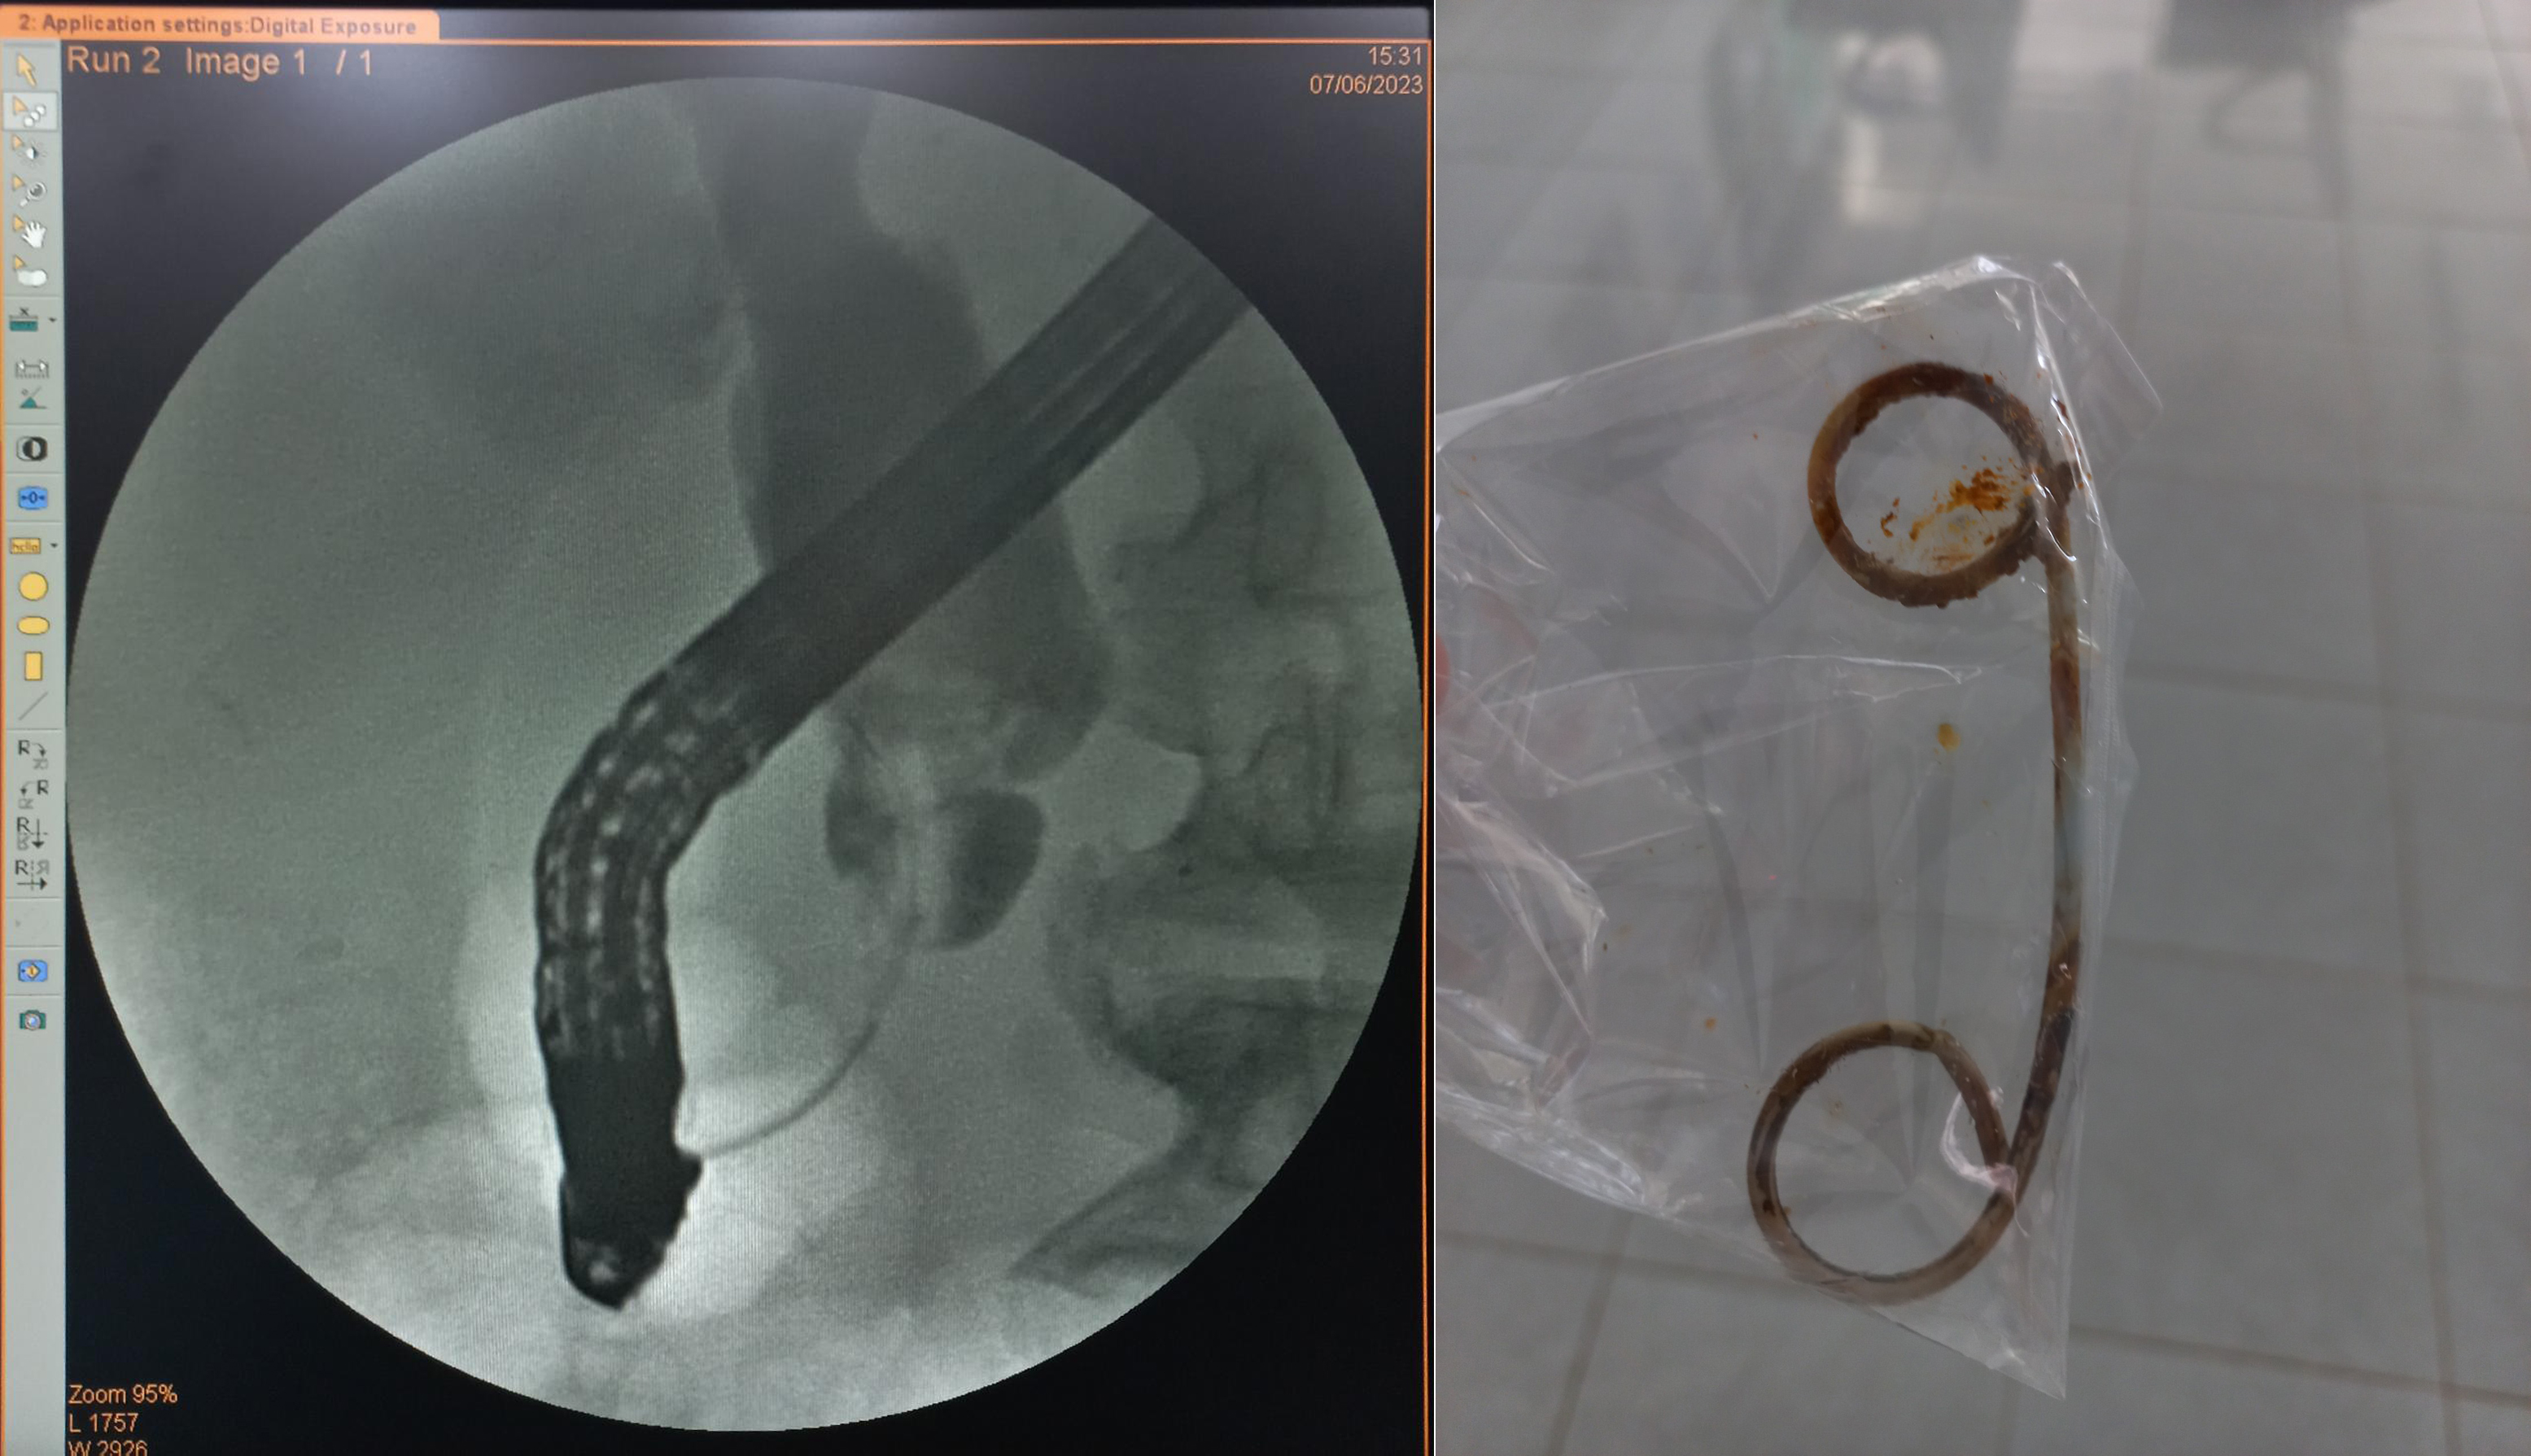

Hình ảnh chụp đường mật bị hẹp đoạn cuối ống mật chủ và stent bị tắc do để quá lâu.

Trong quá trình can thiệp ERCP, nhận thấy đường mật có stent cũ đã tắc và bám sỏi, dịch mật không thoát ra được do hẹp đoạn cuối ống mật chủ, ekip can thiệp đã rút bỏ stent cũ và tiến hành đặt lại 1 stent khác để dẫn lưu ổ nhiễm trùng tạm thời.